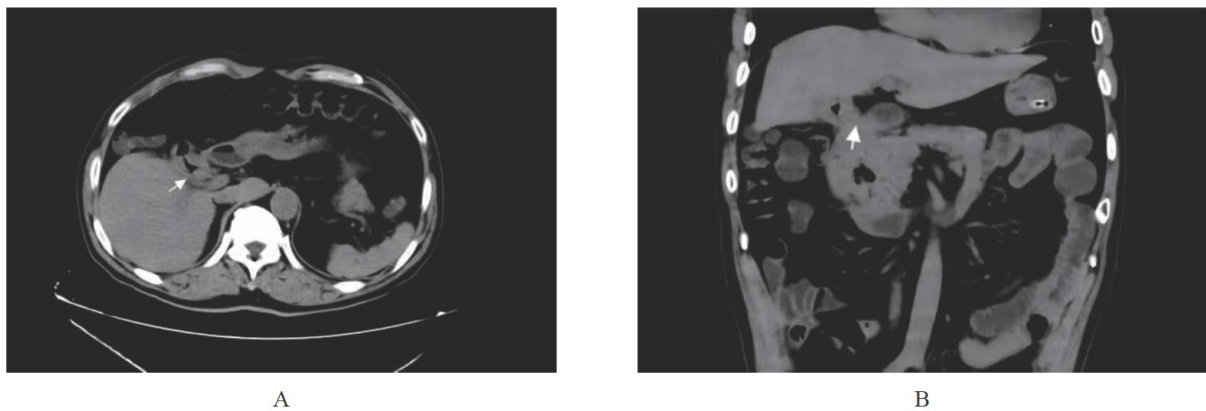

胆囊十二指肠瘘是结石性胆囊炎较为严重的并发症之一,占胆系疾病的 0.5%~1.9%[1] ,所有胆肠瘘的 2/3[2] ,多见于胆囊底部与十二指肠降部之间。(剩余4205字)